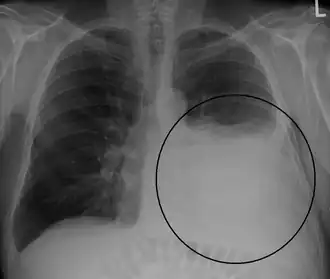

Op een longfoto is pleuravocht zichtbaar als een wit gedeelte op de longfoto.[4] Op een normale thorax foto is de ruimte tussen de viscerale pleura en de pariëtale pleura niet zichtbaar. Wanneer er pleuravocht aanwezig is, is deze ruimte wel zichtbaar. De densiteit van pleuravocht is ongeveer gelijk aan die van water, hierdoor is dit witter op een longfoto in vergelijking met de rest van de long (die meer de densiteit van lucht heeft). Door de hogere densiteit zal pleuravocht zich altijd bevinden op het laagste punt van de thoraxholte en is er een bij horizontale vloeistofspiegel (meniscus).[5] Een longfoto in zijligging (op de zijde waar het pleuravocht zich bevindt) is sensitiever voor pleuravocht. Dit wordt een "decubitus opname" genoemd, bij deze opname wordt een hoeveelheid van 50 ml of meer pleuravocht zichtbaar. Een CT-scan van de borstkas is het meest nauwkeurig voor het bepalen van de aanwezigheid van pleuravocht, maar ook de hoeveelheid en kenmerken van het pleuravocht. Ook echografie kan gebruikt worden om pleuravocht aan te tonen.[6]

Forse hoeveelheid pleuravocht links bij een patiënt met longkanker. -